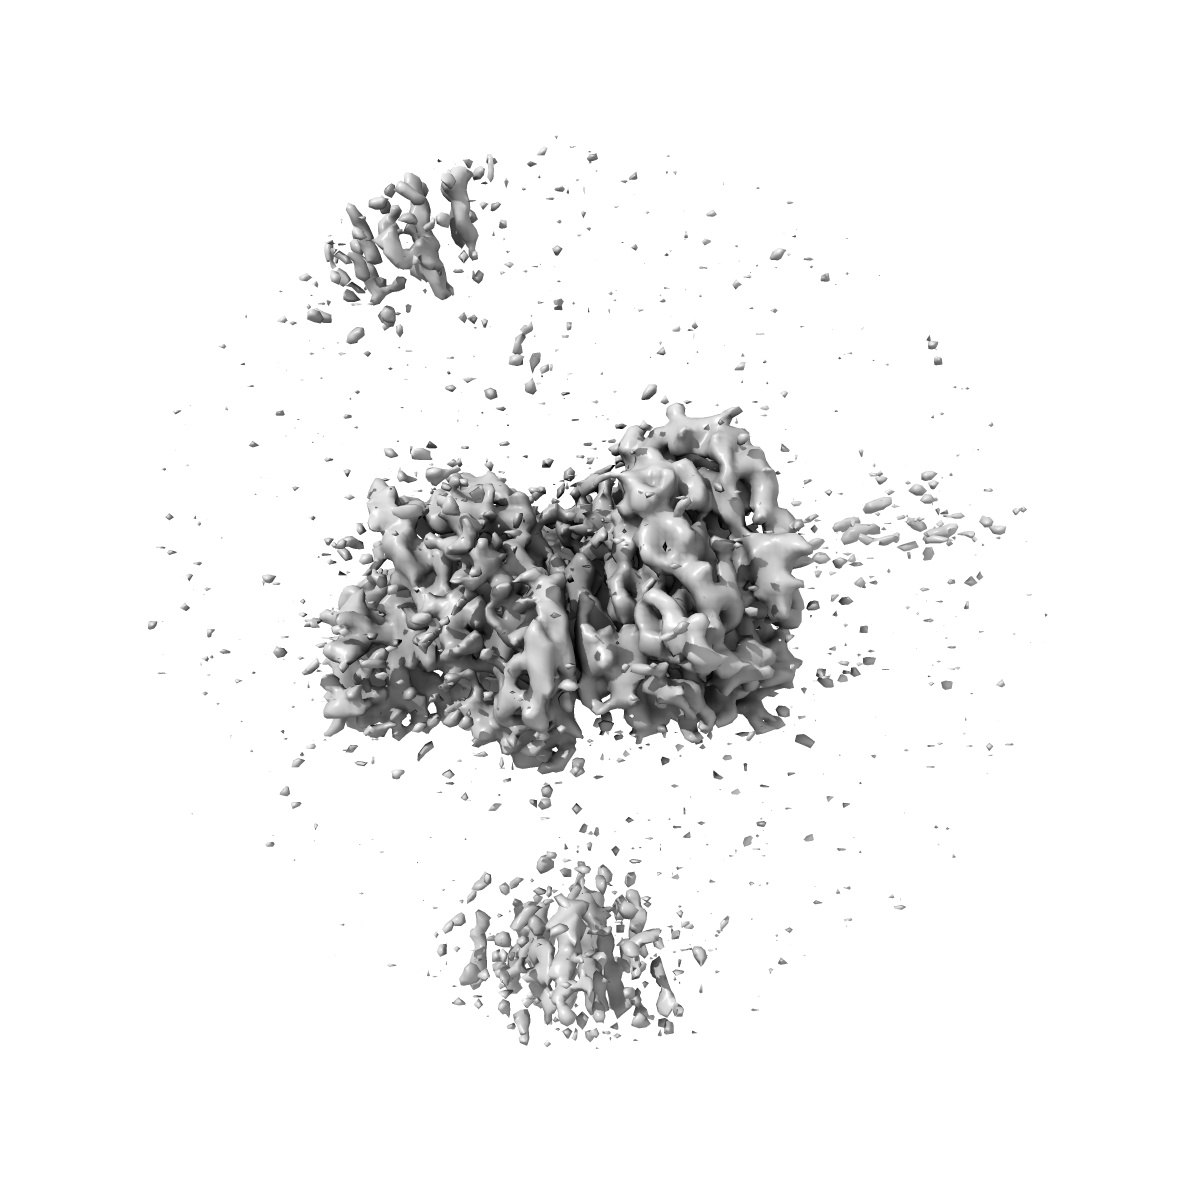

Rapid screening cryo-EM map of CAK bound to ICEC0510-S (grid VC7-4, 1hr collection)

Single-particle3.4 Å

Sample: CDK-activating kinase